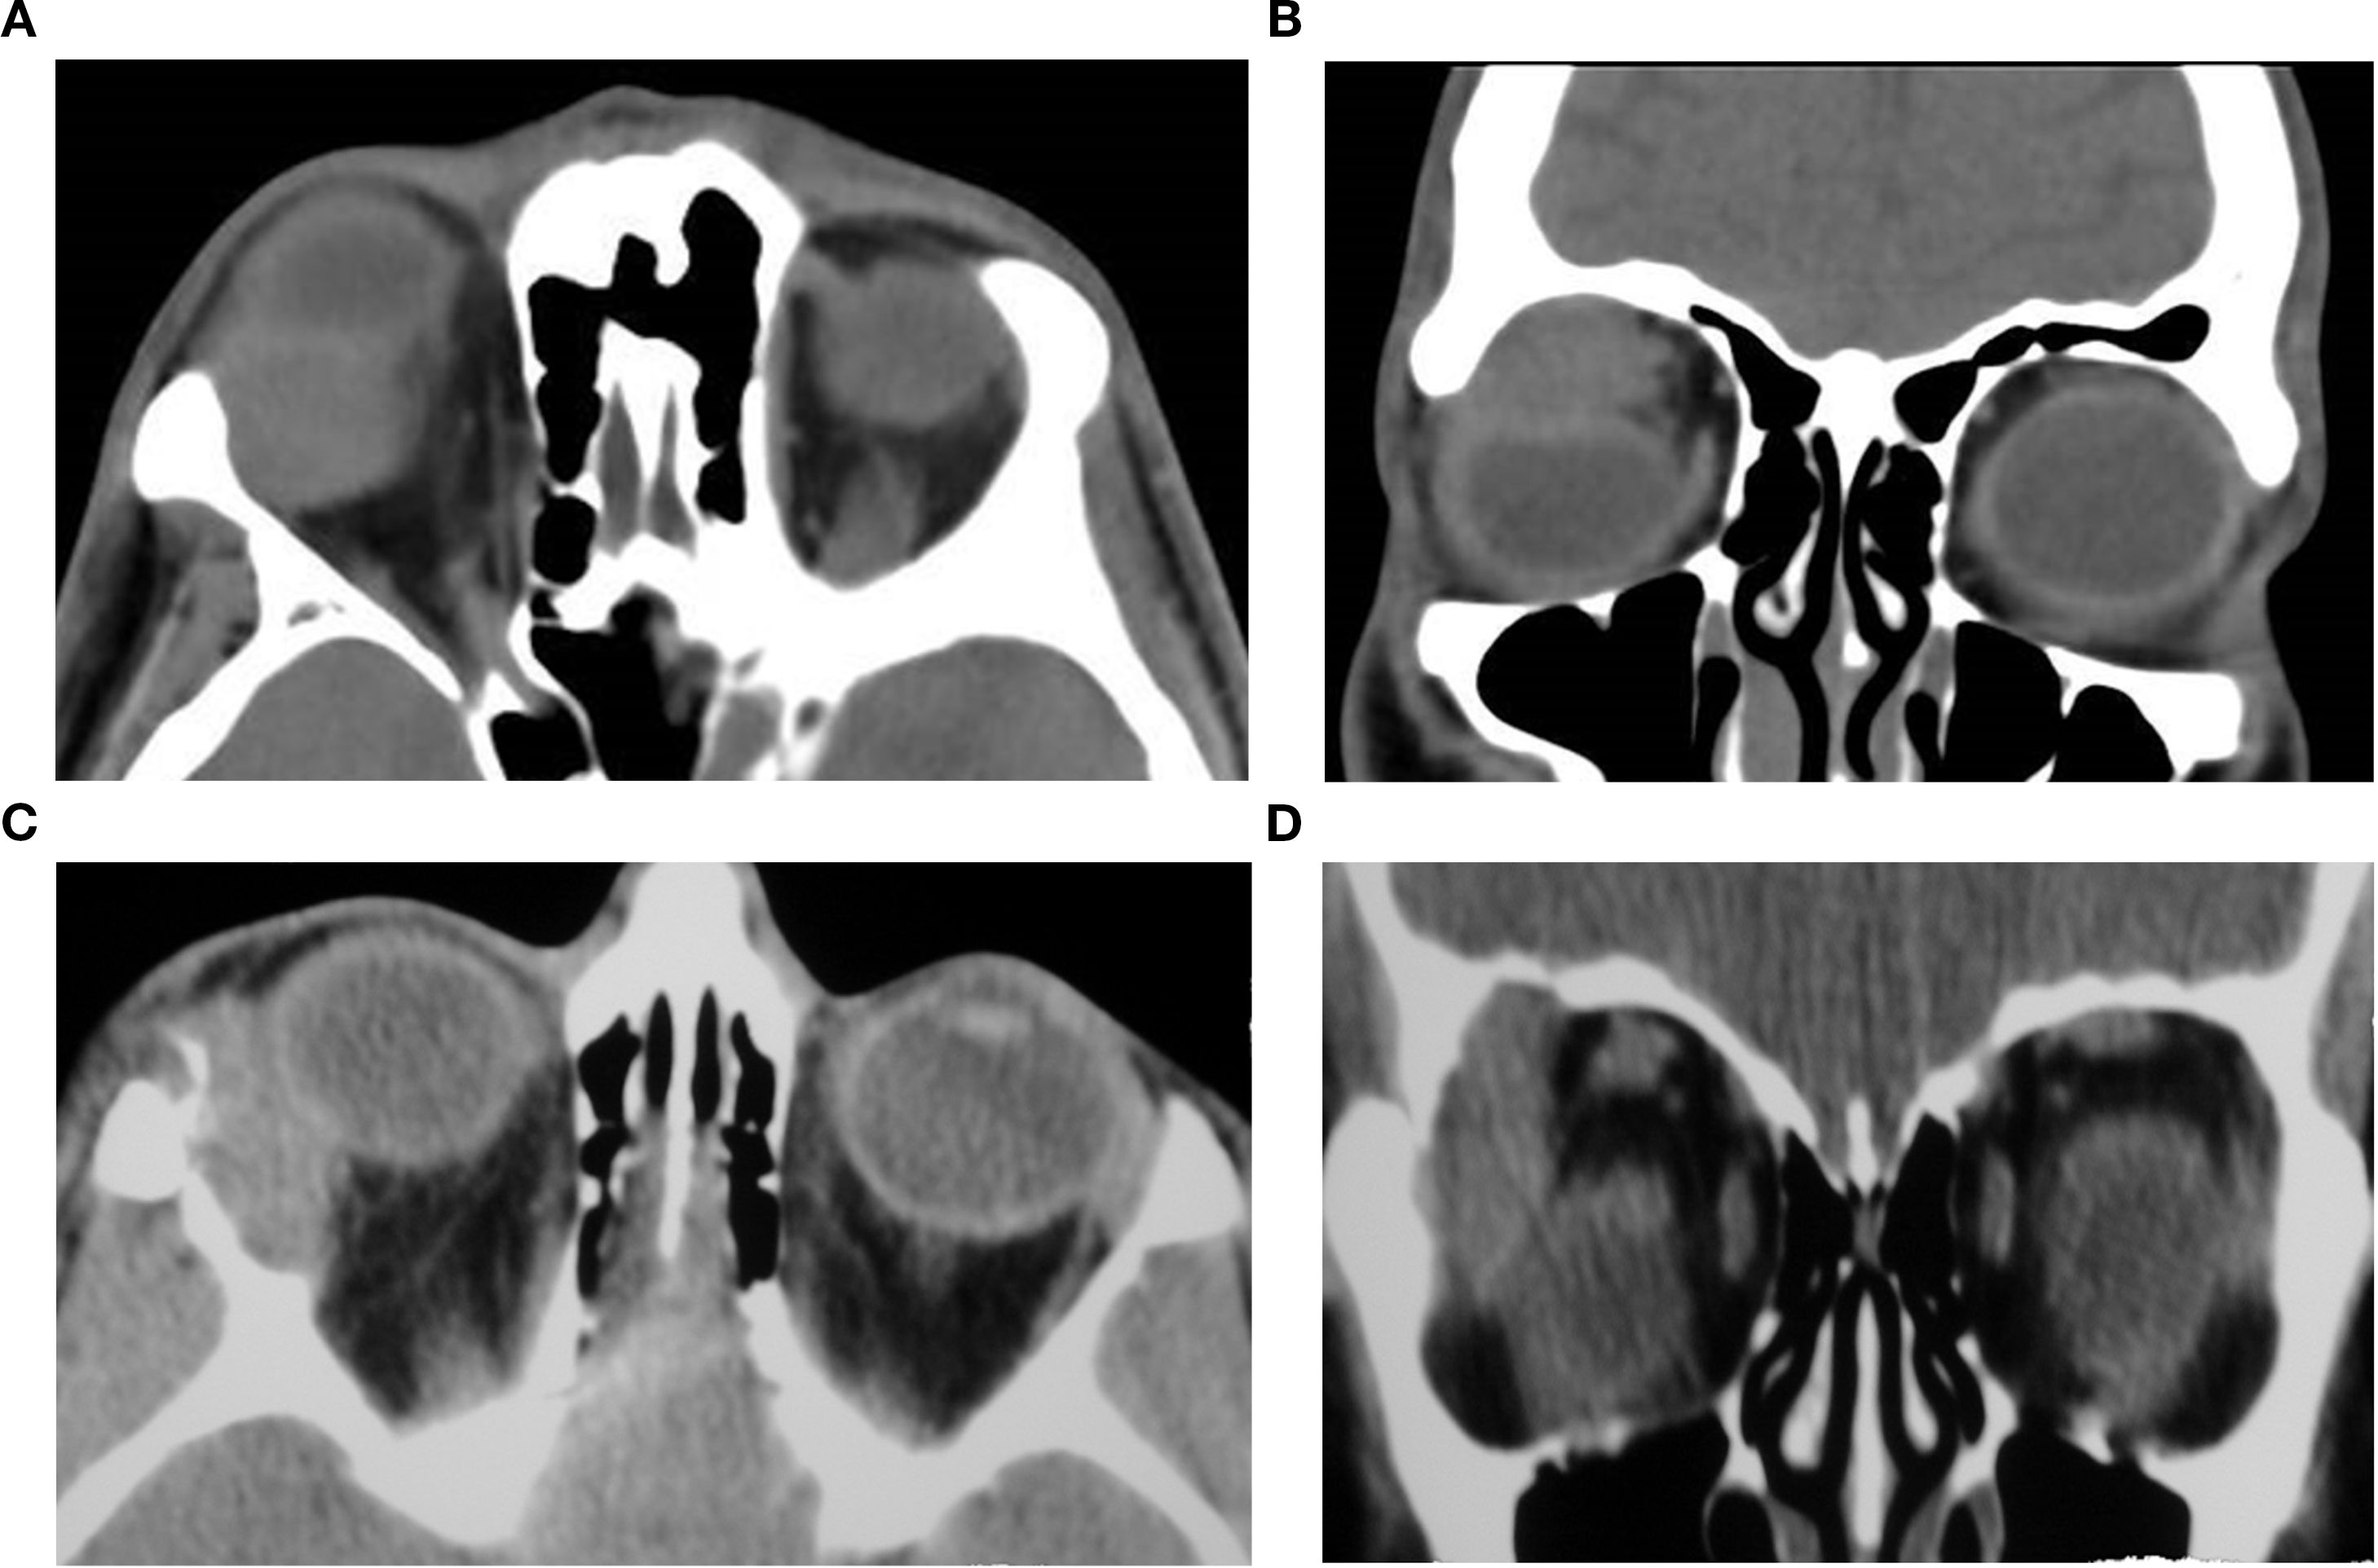

Orbital masses include a diverse spectrum of benign, malignant, inflammatory, and vascular lesions in pediatric and adult patients. Accurately diagnosing the type of lesion is critical, as management strategies differ significantly. Advanced imaging is therefore essential, and computed tomography (CT) is central to orbital evaluation. We reviewed the literature to synthesize evidence on CT features across common orbital pathologies and correlated imaging with clinical presentation to emphasize diagnostic relevance. CT characteristics are summarized for vascular lesions (cavernous venous malformation, lymphatic malformation), inflammatory conditions (orbital myositis, dacryoadenitis), benign lesions (dermoid cyst, pleomorphic adenoma), and malignant lesions (lacrimal gland lymphoma, adenoid cystic carcinoma, rhabdomyosarcoma). We present characteristic patterns of location, morphology, enhancement, and bone change, with practical discriminators and common pitfalls to aid differentiation. When used alongside clinical context, CT remains a preferred modality in many clinical settings due to its rapid acquisition, wide availability, and reliable depiction of bone and calcifications. It supports accurate diagnosis and informed management decisions in time-critical settings. This review provides a structured reference for interpreting CT findings across a wide range of orbital disease.